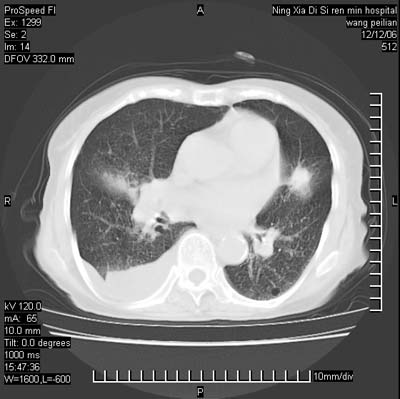

标题: CT5609:胸部:女77 病史不详

两肺可见多个大小不等的结节,左侧有胸水,纵隔淋巴结增大,考虑是细支气管肺泡癌

两肺尖纤维索状影,两下肺结节块状影,且有钙化灶,右胸腔积液。考虑肺结核并胸膜炎。

两肺尖纤维索状影,两下肺结节块状影,且有钙化灶,右胸腔积液。考虑肺结核并胸膜炎肺间质纤维化

考虑:1、慢性支气管炎合并全小叶型肺气肿、间质纤维化;

2、双肺结核;

3、右侧胸膜炎(积液)。

1、双肺继发型肺结核(以纤维、增殖灶为主);

2、右侧胸腔积液;

3、其余符合老年肺改变。

双肺见多个结节状及条索状影,双侧胸腔积液,右侧叶间积液,考虑结核性胸膜炎